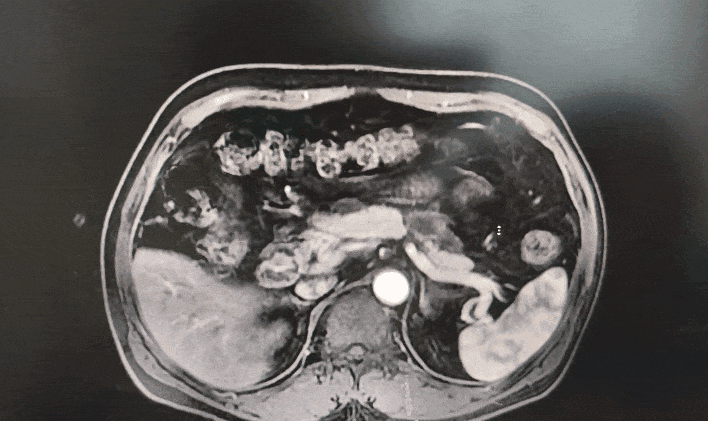

◈ 2022-11-28,TTFields联合化疗治疗2个月,上腹部MR增强扫描,对比基线( 2022-09-13):胰周多发囊性病变,考虑为术后改变(活检后),假性囊肿形成可能,较前略吸收;局部与邻近胃壁分界不清,左侧门脉高压,胃底、肠系膜静脉曲张,脾静脉近段较前显示清楚,肠系膜上动脉、腹腔干近段及局部分支周围软组织影较前范围缩小。

2022-11-28上腹部MR增强扫描—TTFields联合化疗治疗两个月